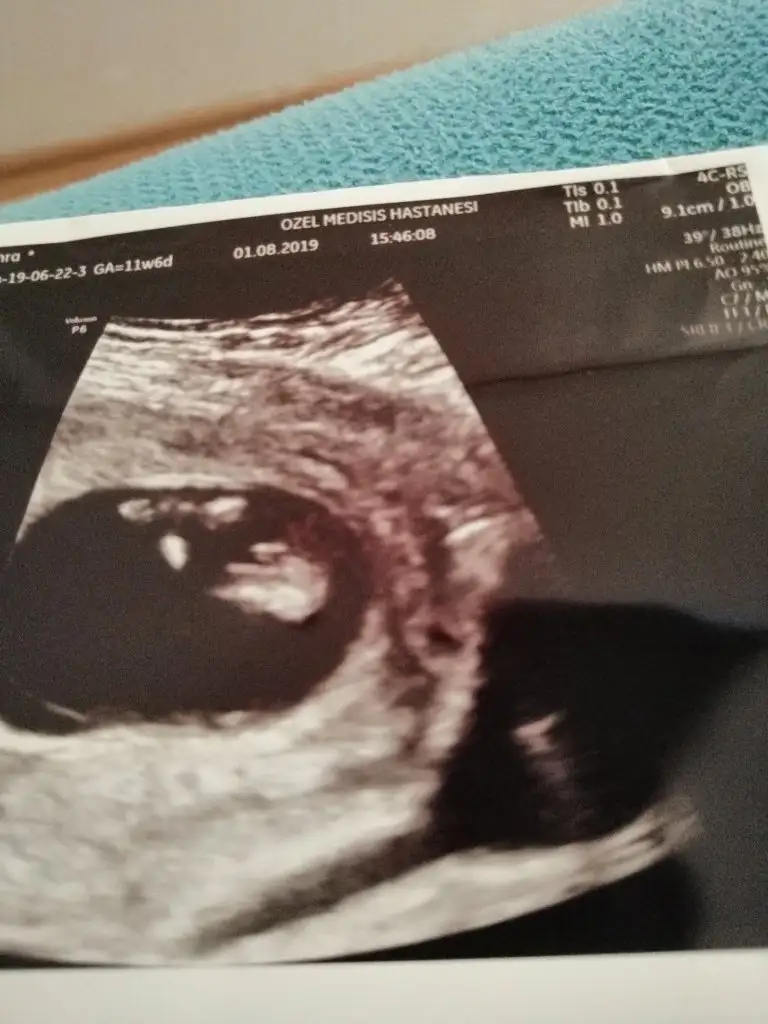

Tamam kız bu bebiş.kesin kızEki Görüntüle 2294615 Eki Görüntüle 2294617

Bunlarda az önce alınan resimler normalde 11 hafta 6 günlük ama usg de 12 hafta 6 günlük

Kızlaar bende çok merak ediyorum geçen hafta 11+5 ken bunlar İpucu veriyormu sizce cinsiyet nedir?

Siz erkek istiyordunuz galiba.nub çizgisine ve kafa yapısına göre yorum yapıyorum.cinsiyet oluşmadan önce nub çizgisi oluşur.bu çizgi paralelse kız,dik ise erkek demektir.sizin bebeğinizin nub çizgisi bariz paralel.kafa yapısı da oval.erkeklerin kafa yapısı daha yuvarlak olur. Doktor kesin erkek dedi mi size? Buda cinsel organı diye gösterdi mi? Kaç haftalıksınız şuan?Doktor organını bile gösterdi bu çıkıntı olabilir diye yine de cevabınız için teşekkür ederim merakımdan soruyorum yanlış anlamayın neye göre Tahminde bulunuyorsunuz mesela son resim tam olarak neyi gösteriyor hiçbirşey anlamadım

Evet gönlümden geçen erkek Bi tane kızım var çok ta sevinmiştim siz şimdi kesin kız deyince moralim bozuldu biraz. Şu an sat a göre 11 hafta 6 gün usg ye göre 12 hafta 6 gün. Doktor erkeğe çok benziyor çıkıntısı burada diyerek gösterdi kesin erkek demedi yüzde 80 erkek dedi ama bazen kızlarda da bu çıkıntı oluyor dedi. Hatta bu Nub teorisinden de bahsettim belli olmaz bazen dik bazen paralel bile olabilir dediSiz erkek istiyordunuz galiba.nub çizgisine ve kafa yapısına göre yorum yapıyorum.cinsiyet oluşmadan önce nub çizgisi oluşur.bu çizgi paralelse kız,dik ise erkek demektir.sizin bebeğinizin nub çizgisi bariz paralel.kafa yapısı da oval.erkeklerin kafa yapısı daha yuvarlak olur. Doktor kesin erkek dedi mi size? Buda cinsel organı diye gösterdi mi? Kaç haftalıksınız şuan?

Kızlarda da bu çıkıntı oluyor dediyse nub çizgisinden bahsediyor.11 12 haftada cinsel organ tam anlamıyla oluşmuyor nub çizgisi oluyor.13 14 haftalarda organ oluşmuş oluyor.yani direkt olarak pipi göstermemiş.bilmiyorum doktor erkek dediyse erkek olabilir.ben bariz kız görüyorum bu usg de.elbette doktorlar daha iyi bilir tabi.rabbim gönlünüzdekileri nasip etsin inşallah.siz sorduğunuz için cevapladım.ama bana göre bu bebiş kızEvet gönlümden geçen erkek Bi tane kızım var çok ta sevinmiştim siz şimdi kesin kız deyince moralim bozuldu biraz. Şu an sat a göre 11 hafta 6 gün usg ye göre 12 hafta 6 gün. Doktor erkeğe çok benziyor çıkıntısı burada diyerek gösterdi kesin erkek demedi yüzde 80 erkek dedi ama bazen kızlarda da bu çıkıntı oluyor dedi. Hatta bu Nub teorisinden de bahsettim belli olmaz bazen dik bazen paralel bile olabilir dedi